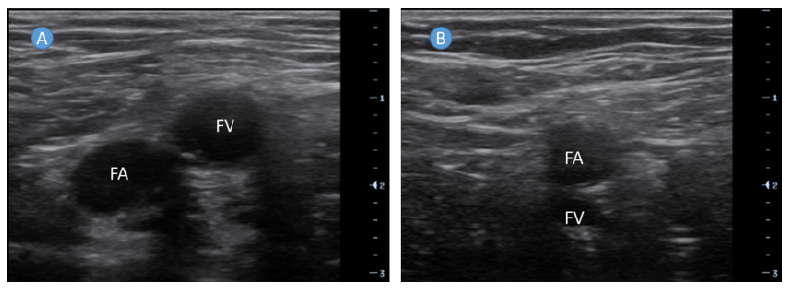

Femoral Arteriovenous Fistula Following Removal of Femoral Vein Catheter: A Case Report

Zhiming Zhang, Yuan Qin and Huidan Ouyang. 6(9): 01-03.